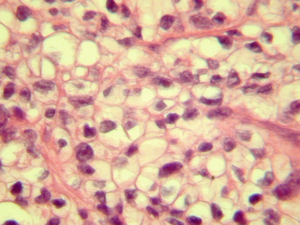

Krabbe disease (Globoid Cell Leukodystrophy):

Deficiency of the lysosomal enzyme **beta galactocerebrosidase;

CNS pathology due to accumulation of psychosine–> loss of oligodendrocytes, myelin

Histo:

- numerous globoid cells, paucity of intact myelin and oligodendrocytes and variable loss of axons.